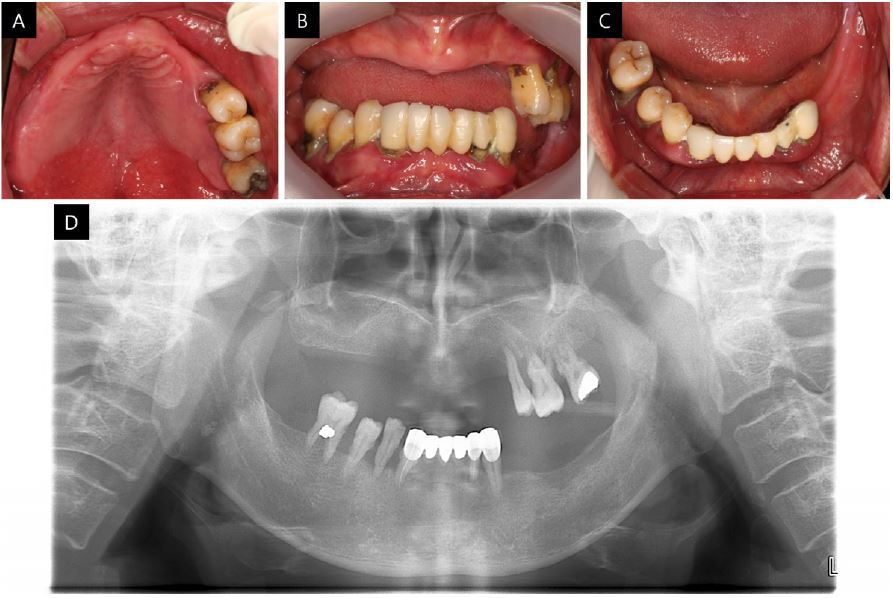

The patient presented in this case was a 64-year-old man with diabetes and hyperlipidemia, with a chief request for implant-supported restoration in the edentulous area. In the intra-oral examination, all remaining teeth had signs of severe chronic periodontitis and had erupted beyond the occlusal plane where extraction was inevitable (Fig. 1). The patient presented with decreased height of the lower third of the face, lack of lip support, wrinkles, and drooping commissures around the corner of the mouth.